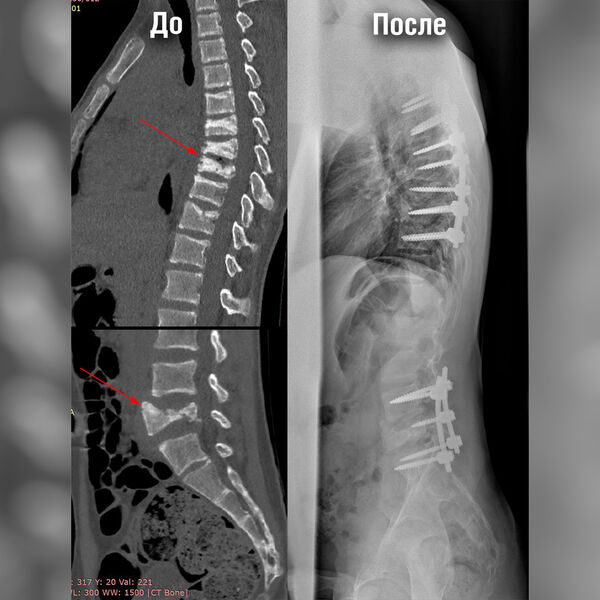

Мальчику провели комплекс обследований, в том числе КТ и МРТ позвоночника, по результатам которых врачи обнаружили компрессионные переломы позвонков в грудном и поясничном отделе. Для проведения экстренной операции по фиксации переломов врачам необходимо было стабилизировать состояние пациента.

Стандартным подходом к лечению компрессионных переломов позвоночника является транспедикулярная фиксация при помощи металлоконструкции — сложная высокотехнологичная операция.

«Мы получили доступ к области переломов, установили в тела позвонков специальные винты, после чего соединили их стержнями. Всего было установлено две металлоконструкции — протяженностью в семь позвонков грудного отдела и в три позвонка поясничного. Затем мы уложили их костным аутотрансплантатом, чтобы обеспечить максимальную стабильность в дальнейшем», — рассказал о ходе оперативного вмешательства Андрей Пантелеев.